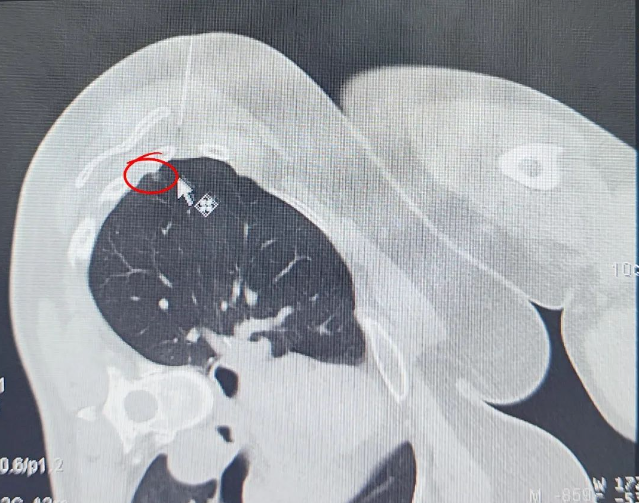

定位技術(shù)升級(jí)通過 CT 影像精準(zhǔn)鎖定 6mm 磨玻璃結(jié)節(jié)(圖示可見),全程在麻醉狀態(tài)下完成定位操作,顯著降低傳統(tǒng)清醒定位可能引發(fā)的患者緊張情緒及轉(zhuǎn)運(yùn)風(fēng)險(xiǎn)。微創(chuàng)技術(shù)突破運(yùn)用精細(xì)化微創(chuàng)操作分離粘連組織,在切除病灶過程中精準(zhǔn)避讓正常肺組織,經(jīng)術(shù)后影像評(píng)估,實(shí)現(xiàn)病灶完整清除與健康肺功能保留的平衡。